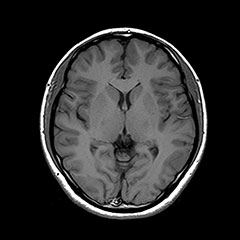

MRI

脳卒中、脳腫瘍、脳萎縮、白室病変、脳室拡大

日本脳ドック学会の推奨する検査内容となります。 頭部MRI検査(T1WI, T2WI, FLAIR, T2*)、頭部MRA検査、頚動脈MRA検査、血液検査、尿検査、心電図検査を行います。

脳ドック基本コースに加え記憶領域を司るといわれる海馬の検査を行います。早期アルツハイマー型認知症が確認できます。

早期の認知症 では最も早く海馬傍回(記憶に関わる部位) が萎縮することがわかっています。MRI画像を利用し、この海馬傍回の体積の萎縮度を正常脳と比較します。また認知症のなかでも手術で良くなる可能性がある正常圧水頭症の有無も併せて確認できます。